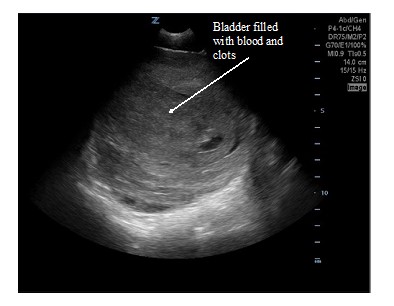

An 18-year-old male was brought in by EMS with a penetrating stab wound to his left buttock from an unknown weapon. Blood was oozing from the stab wound entry site, but he was hemodynamically stable. Shortly after arrival to the emergency department, he developed frank hematuria. An initial FAST exam revealed a large clot within the bladder walls (Fig. 1) but was negative for intraabdominal free fluid. A large hematuria catheter was placed by Urology to evacuate this clot. CT and CT angiogram of the abdomen and pelvis revealed active bleeding within and adjacent to the left posterior bladder wall, as well as a clot filled bladder and a deep pelvic hematoma displacing the rectum. A CT cystogram revealed no filling defect within the distal ureters or extravasation of contrast to suggest intra- or extra-peritoneal bladder rupture. After CT imaging, Urology copiously irrigated the bladder with normal saline to remove the clot. During irrigation, the patient developed significant abdominal pain and distension. A repeat FAST exam was performed revealing free fluid in the right upper quadrant (Fig. 2), left upper quadrant (Fig. 3), and pelvis (Fig. 4). The pelvic view also revealed an enhanced peritoneal stripe sign (Fig. 4) suggesting pneumoperitoneum.

Figure 1. Transverse suprapubic view of the initial FAST. A well-circumscribed structure with mixed echogenicity is seen, which is the bladder filled with blood and clots.